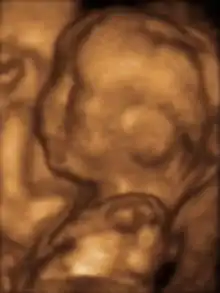

Fetus at 17 weeks

Fetus at 20 weeks

Fetal assessments

Obstetric ultrasonography is routinely used for dating the gestational age of a pregnancy from the size of the fetus, determine the number of fetuses and placentae, evaluate for an ectopic pregnancy and first trimester bleeding, the most accurate dating being in first trimester before the growth of the foetus has been significantly influenced by other factors.[22] Ultrasound is also used for detecting congenital anomalies (or other foetal anomalies) and determining the biophysical profiles (BPP), which are generally easier to detect in the second trimester when the foetal structures are larger and more developed.[23]

X-rays and computerized tomography (CT) are not used, especially in the first trimester, due to the ionizing radiation, which has teratogenic effects on the foetus.[24] No effects of magnetic resonance imaging (MRI) on the foetus have been demonstrated,[25] but this technique is too expensive for routine observation. Instead, obstetric ultrasonography is the imaging method of choice in the first trimester and throughout the pregnancy, because it emits no radiation, is portable, and allows for realtime imaging.[26]

The safety of frequent ultrasound scanning has not been confirmed. Despite this, increasing numbers of women are choosing to have additional scans for no medical purpose, such as gender scans, 3D and 4D scans.[27] A normal gestation would reveal a gestational sac, yolk sac, and fetal pole.[28]

The gestational age can be assessed by evaluating the mean gestational sac diameter (MGD) before week 6, and the crown-rump length after week 6. Multiple gestation is evaluated by the number of placentae and amniotic sacs present.[29]